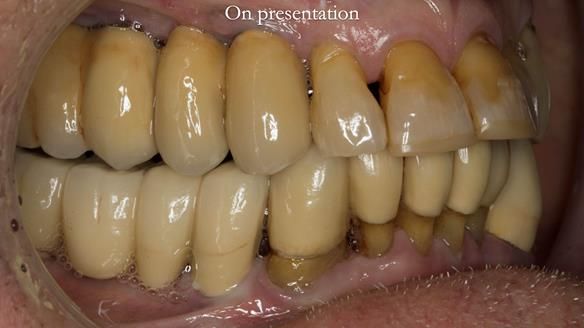

Ken – going downhill, first class

I first met Ken in 2015, when he was 80 years old.

He was a wonderful person.

Ken had flown Lightning jets for the RAF and later Boeing 747s for BOAC, which became British Airways. He was thoughtful, sharp, and full of stories.

He had lived in both the UK and the USA, spending many years in Florida, where he received extensive dental and periodontal care.

The starting point

We began with the lower jaw.

Final thoughts

This case was always about function, not aesthetics.

Ken’s teeth were never going to look perfect.

There were stained composites, old restorations, and obvious wear.

That was accepted from the outset.